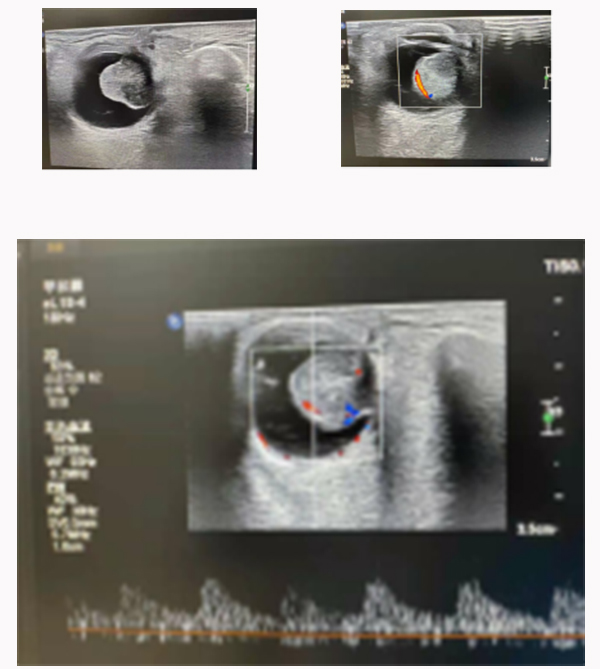

上圖是1例脈絡(luò)膜黑色素瘤患者,彩超檢查:可探及球內(nèi)隆起實(shí)性病變,邊界清晰,內(nèi)回聲不均勻?yàn)橹械突芈,挖空?+)。CDFI:玻璃體內(nèi)病變中可探及較豐富的血流信號,脈沖多普勒為動脈型血流頻譜